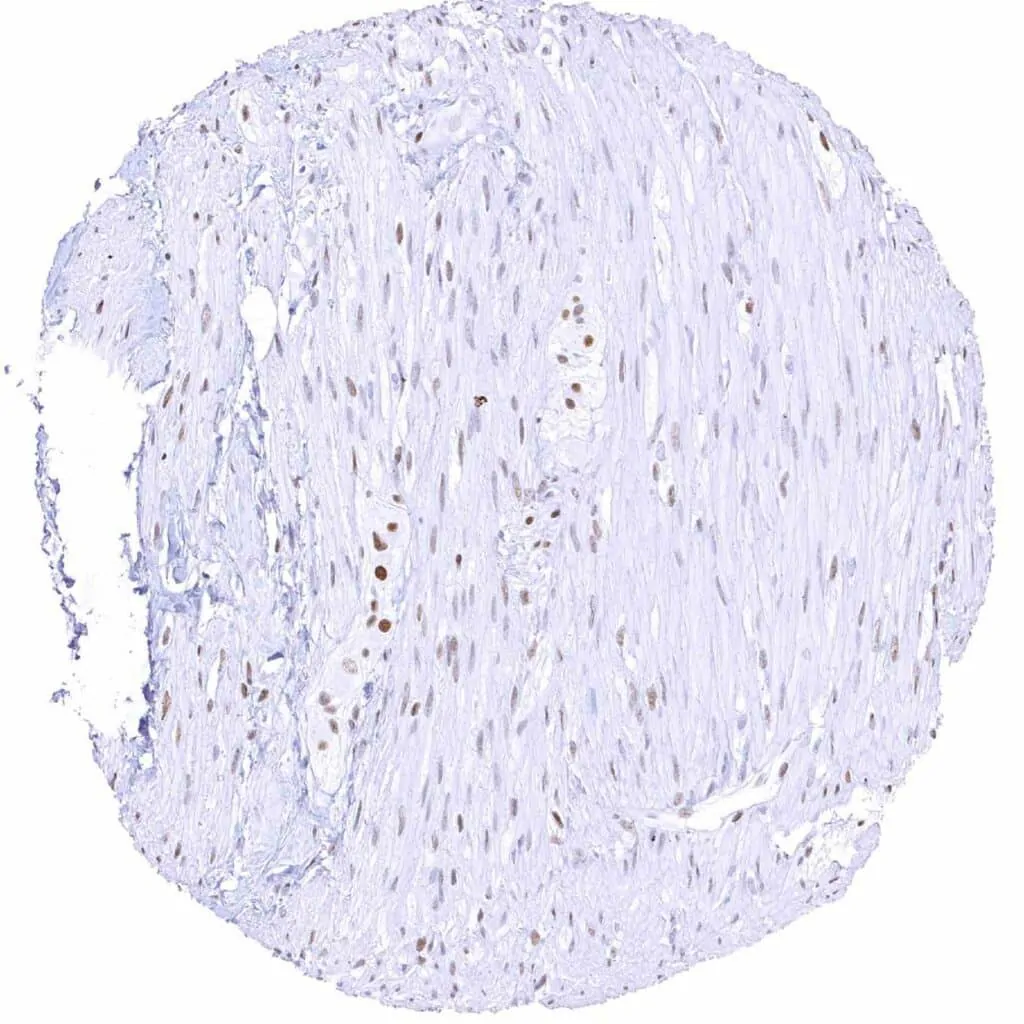

Aorta, media – Moderate TLE1 positivity of a subset of spindle cells in the media